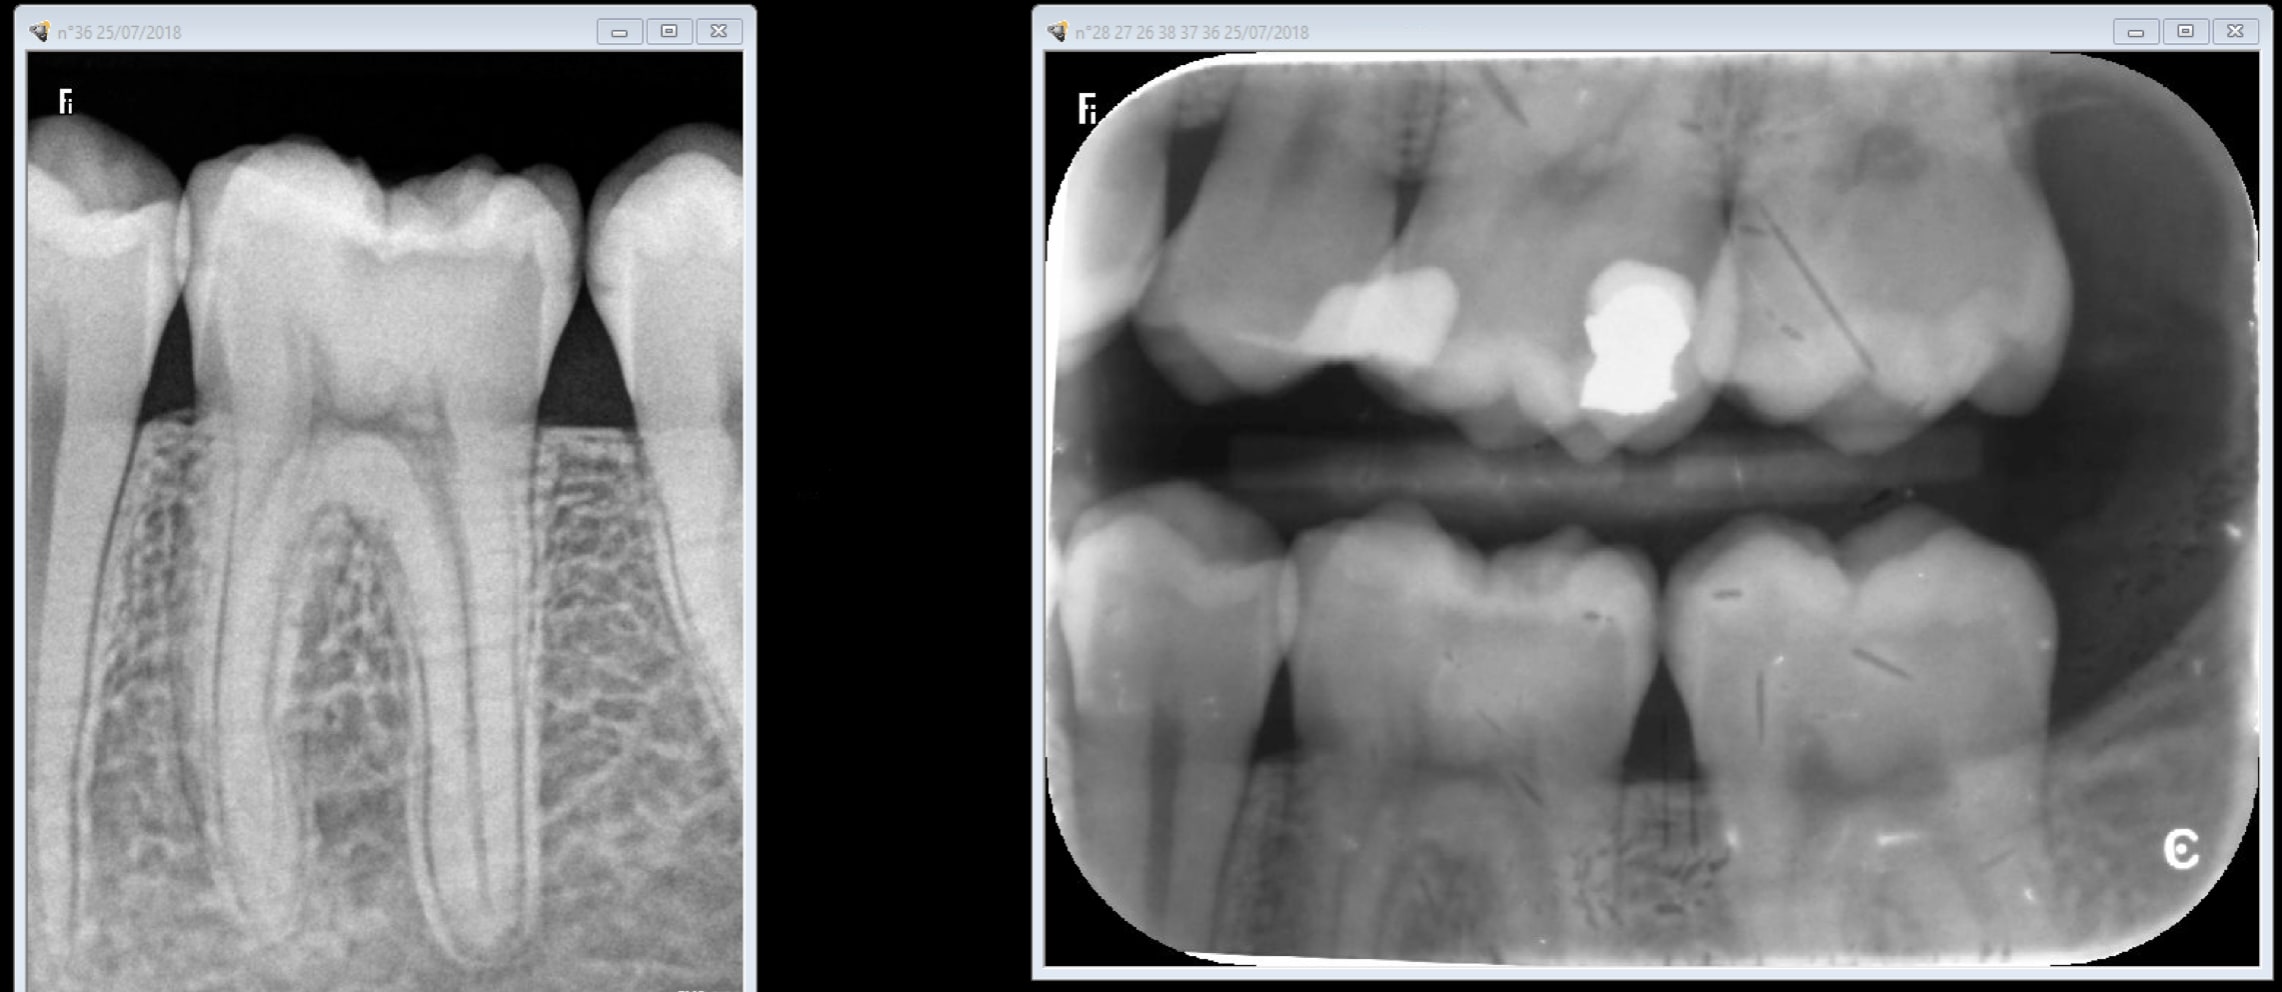

Exemple nouveau patient consulte pour problème sur 36. 1 radio rétroalvéolaire 36 indication carie pénétrante(capteur) , 2 anesthésie 3 rétrocoronaires indication : recherche de caries ( plaques) 4 compo 36.

Regardes moi la qualité de merde que ca te sort un système à plaques. C'est completement inconstant. Il n'y a pas photo. -)))

Le comparatif de mire de cyber_, quand meme, c'est un peu plus rigoureux. Tu prends tes angulations differentes, on ne connait pas l'etat de ta plaque, les deux systemes ont ils le meme age?

Le stratagème est gros ! Tu nous montres un cliché de capteur rétroalvéolaire , avec une accentuation de netteté logiciel au maximum, d'un côté, avec un cliché rétrocoronaire d'une plaque pourrie ( cf défauts de surface), sans accentuation de netteté !!

OK une autre plaque faut jouer avec les filtres avec le capteur non. Ca se ruine assez vite les plaques et ça vaut la peau du derche. Excuses moi le capteur est plus vieux de 5 ans que ces plaques de merde.

Capture d écran 2018 07 25 20.21 - Eugenol

C'est un constat plaques vieilles ou pas plus de boulot à tirer un cliché valable ( gestion du temps d'expo par ex, faire gaffe à ce qu'elles ne prennent pas la lumière au développement ensacheter dés-ensacheter). Le capteur c'est 0,09 s de temps d'exposition point barre. J'ai les 2 bordel pour moi il n'y a pas photo. Faut pas acheter des capteurs de merde non plus. Quand t'en fais 2 dans ta journée tu peux t'appliquer mais quand t'en fais 50 ca commence à etre casses burnes. -)))